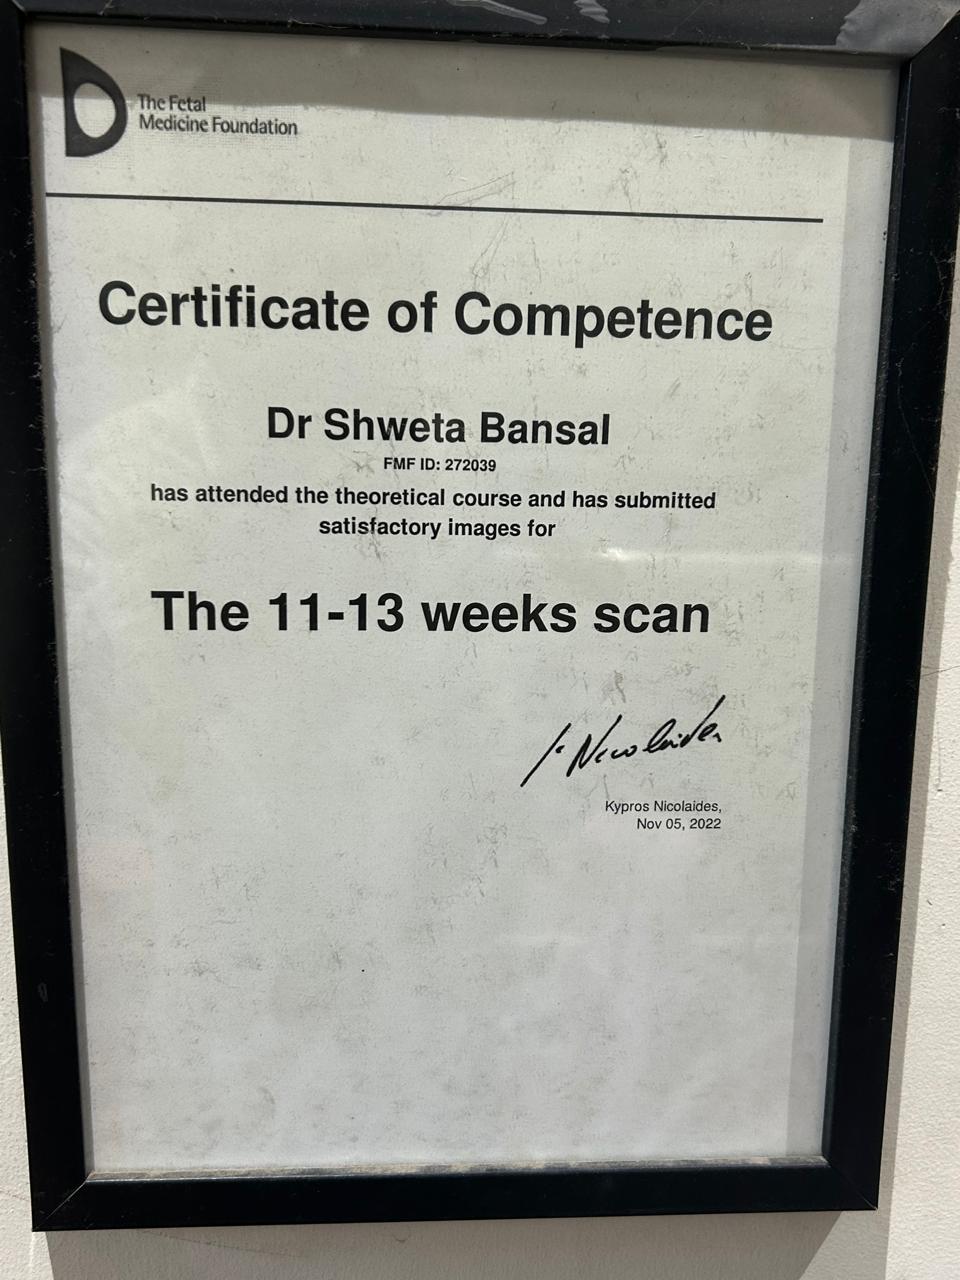

Dr. Shweta Diagnostic & Child Care Centre

Expert Care in Fetal Medicine, Pediatrics & Diagnostics